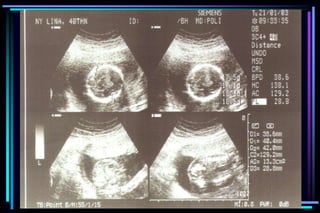

Evaluation of ultrasoundto determine gestational age  Crown Rump Length (CRL)  Biparietal diameter (BPD)  Femur Length (FL)  Head Circumference (HC)  Abdominal Circumference (AC)

Accuracy of ultrasoundmeasurement for different gestational groups Ultrasound parameter Accuracy  Gestational sac diameter + 7 days  Crown Rump Length + 3-5 days  BPD second trimester + 1 to 1.5 weeks  BPD third trimester + 2 to 4 weeks  FL second trimester + 1 to 1.5 weeks  FL third trimester + 3 to 3.5 weeks  Multiple parameter (2nd trimester) + 1.5 weeks  Multiple parameter (3rd trimester) + 2.5 weeks